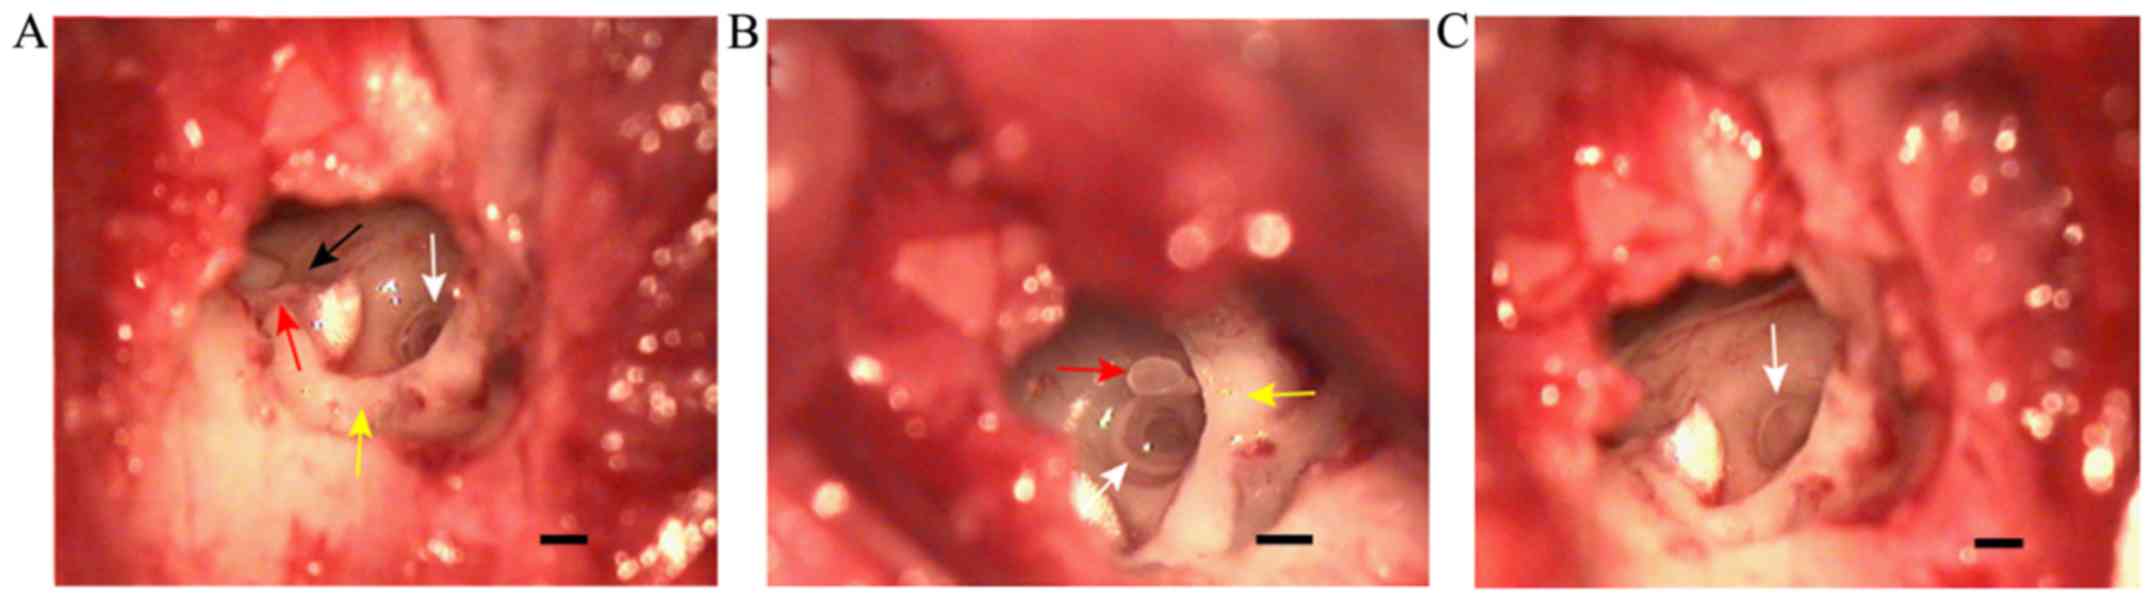

Observation of the tympanic membrane in rabbits under a surgical microscope

The tympanic incisure in the posterosuperior part of the bony auditory canal was covered by pars flaccida, which was thick and exhibited movement with respiration (Fig. 2A). Pars tensa was semicircular and fixed, forming a sharp angle with the external auditory canal. This portion of the tympanic membrane was thin and tightly connected with the malleus, and the handle of malleus was observed through it (Fig. 2A). The interface between pars tensa and pars flaccida formed the anterior malleolar fold and the posterior malleolar fold, which were visible beyond pars tensa (Fig. 2A). After lifting the skin of the external auditory canal, the handle of the malleus and the chorda tympani nerve were observed (Fig. 2B). Furthermore, a part of the lenticular process of the incus and the incudostapedial joint were observed following adjustment of the microscopic angle (Fig. 2C). A part of the posterosuperior wall of the auditory canal was removed to completely expose the ossicular chain composed of malleus, incus and stapes (Fig. 2D).

Figure 2.

Anatomy of the middle ear in rabbits. (A) The anterior malleolar fold (yellow arrow), posterior malleolar fold (black arrow) and the handle of malleus (red arrow) were observed using a microscope through the external auditory canal. The tympanic incisure in the posterosuperior part of the external auditory canal was marked by a blue line and covered by the pars flaccida. (B) The chorda tympani nerve (white arrow) crossing under the malleus was observed after raising the skin flap of the external auditory canal. (C) The malleus (black arrow) and incus (white arrow). The posterosuperior bony part of the external auditory canal was marked by a blue line and was subsequently removed for complete exposure of the entire ossicular chain. (D) Following the removal of the marked bone, the ossicular chain, including the malleus (black arrow), incus (white arrow) and stapes (red arrow) was exposed. Scale bar=0.50 mm.